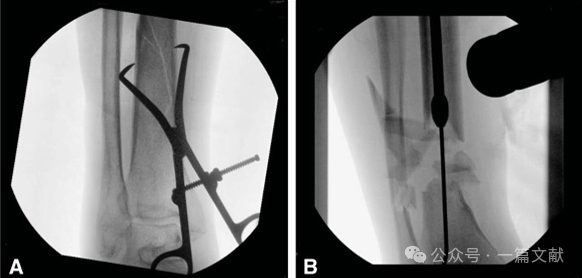

图8,阻挡螺钉:(也称为“Poller”螺钉)是骨折复位的有效辅助工具,可以在髓内钉置入前预防性地放置,也可以在髓内钉置入后出现畸形时使用。

(A) 在本例中,髓内钉置入后出现了向前成角畸形(procurvatum deformity)。

(B) 在畸形的凹侧后方放置了一枚阻挡螺钉,实现了适当的矫正。